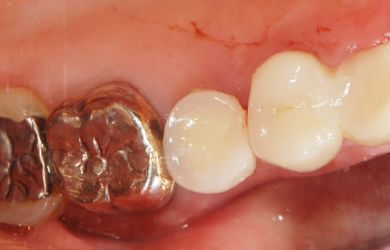

カテゴリー 【インプラント治療】【セラミック治療】

性別/年齢 女性 / 57歳

主訴 さし歯がグラグラしている。

治療方針 ブリッジの支えとなっている歯の寿命を延ばすため、ブリッジの部分を切断し、インプラント治療を施す。

治療内容 インプラント1本、ハイブリッドセラミック1本、ジルコニアオールセラミック8本

治療前

治療後